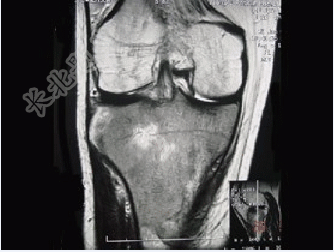

- 单项选择题患者女,28岁,右膝跌伤伴疼痛9年,加重及活动障碍1年半,经药物治疗及理疗后病情无好转,既往无特殊病史,查体跛行步态,触痛,请结合所提供的图像,选择最佳选项( )

A、骨巨细胞瘤

B、结核

C、骨肉瘤

D、滑膜肉瘤

E、软骨肉瘤